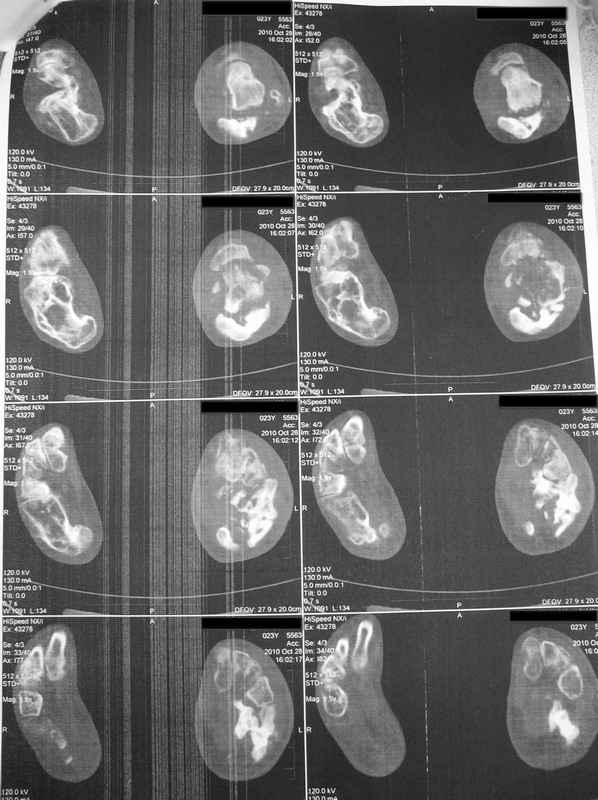

Молодая девушка со сросшимися многооскольчатыми переломами пяток и голеней.

Young girl with fractures of the calcaneus

Больная Н., 25 лет, падение с высоты (2008 г.). Жалобы на боли в области голеностопных суставах, в области пяток при ходьбе. Лечилась в аппаратах внешней фиксации по поводу открытых оскольчатых переломов обеих голеней, переломов пяток. Далее по поводу несросшихся переломов голеней –ЧКОС аппаратами внешней фиксации. Переломы срослись, аппараты демонтированы весной 2010г. В левой пяточной области в месте проведения спицы имеется сукровичное отделяемое. При ревизии гноя нет. Чем помочь девушке?

Patient N., age 25, falls from heights (2008). Complaints of pain in the ankles, in the heel when walking. She was treated by external fixation on open comminuted fractures of both legs, fractures of the calcaneus. Then she was treated by external fixation from nonunion of both legs. Now fractures are fused, apparatuses removed in the spring of 2010. How to help a girl?